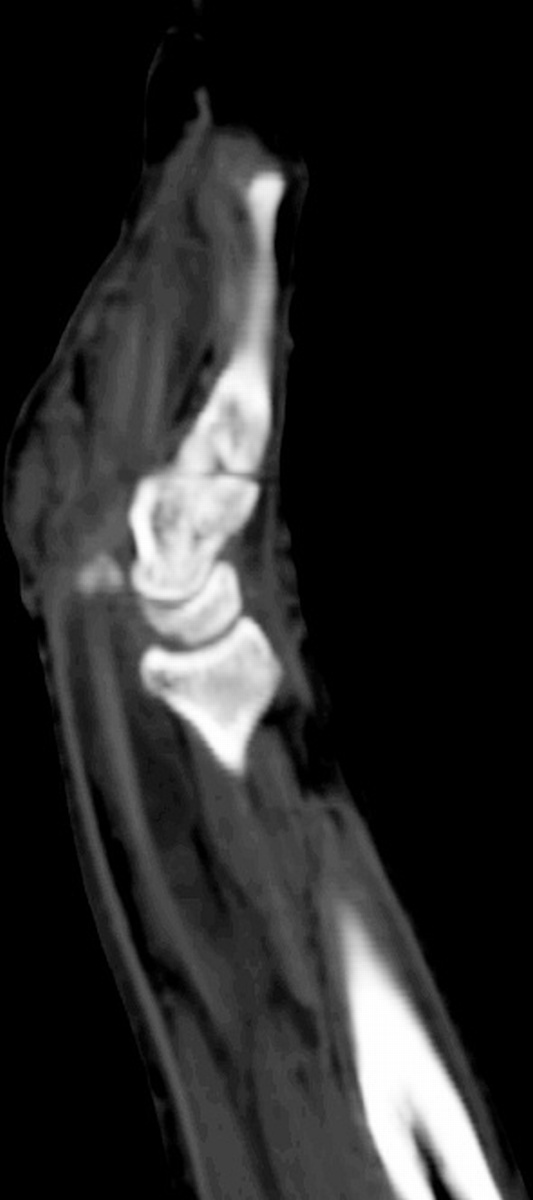

The radiologist  interpreted his MRI as normal, but these views show bulky, edematous flexor synovitis.